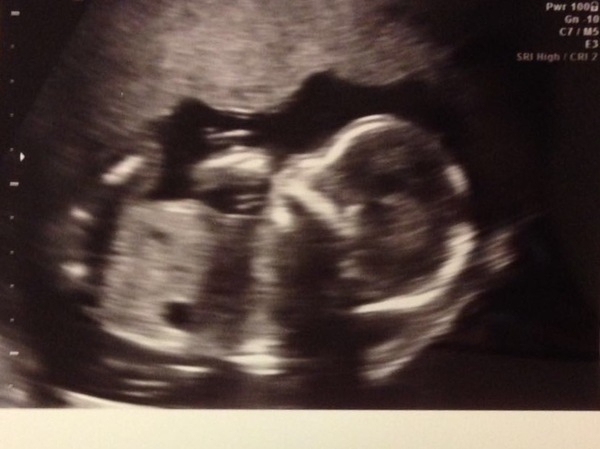

We had ours today, at 18+5, picture attached. All measured ok (head is a week bigger, hope that corrects itself!) and he's a little boy! He kept wriggling about & putting his hands in front of his face, did not like being prodded & looked at! We were lucky in that the sonographer didn't rush, talked us through each measurement & was so lovely.

Fab photo @tmc14

Lovely photo @tmc14 and yes feeling v relieved thank you :-)